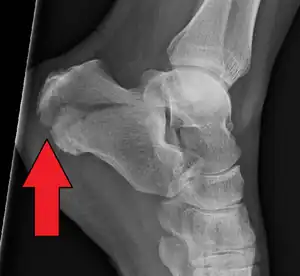

Conventional radiography is usually the initial assessment tool when a calcaneal fracture is suspected. Recommended x-ray views are (a) axial, (b) anteroposterior, (c) oblique and (d) views with dorsiflexion and internal rotation of the foot. However, conventional radiography is limited for visualization of calcaneal anatomy, especially at the subtalar joint. A CT scan is currently the imaging study of choice for evaluating calcaneal injury and has substituted conventional radiography in the classification of calcaneal fractures.[12] Axial and coronal views are obtained for proper visualization of the calcaneus, subtalar, calcaneocuboid and talonavicular joints.

The Angle of Gissane, or "Critical Angle", is the angle formed by the downward and upward slopes of the calcaneal superior surface. On a lateral radiograph, an angle of Gissane > 130° suggests fracture of the posterior subtalar joint surface. Bohler's angle, or the "Tuber Angle", is another normal anatomic landmark seen in lateral radiographs. It is formed by the intersection of 1) a line from the highest point of the posterior articular facet to the highest point of the posterior tuberosity, and 2) a line from the former to the highest point on the anterior articular facet. Bohler's angle is normally 25° to 40°.[13] A decreased angle is indicative of a calcaneal fracture.